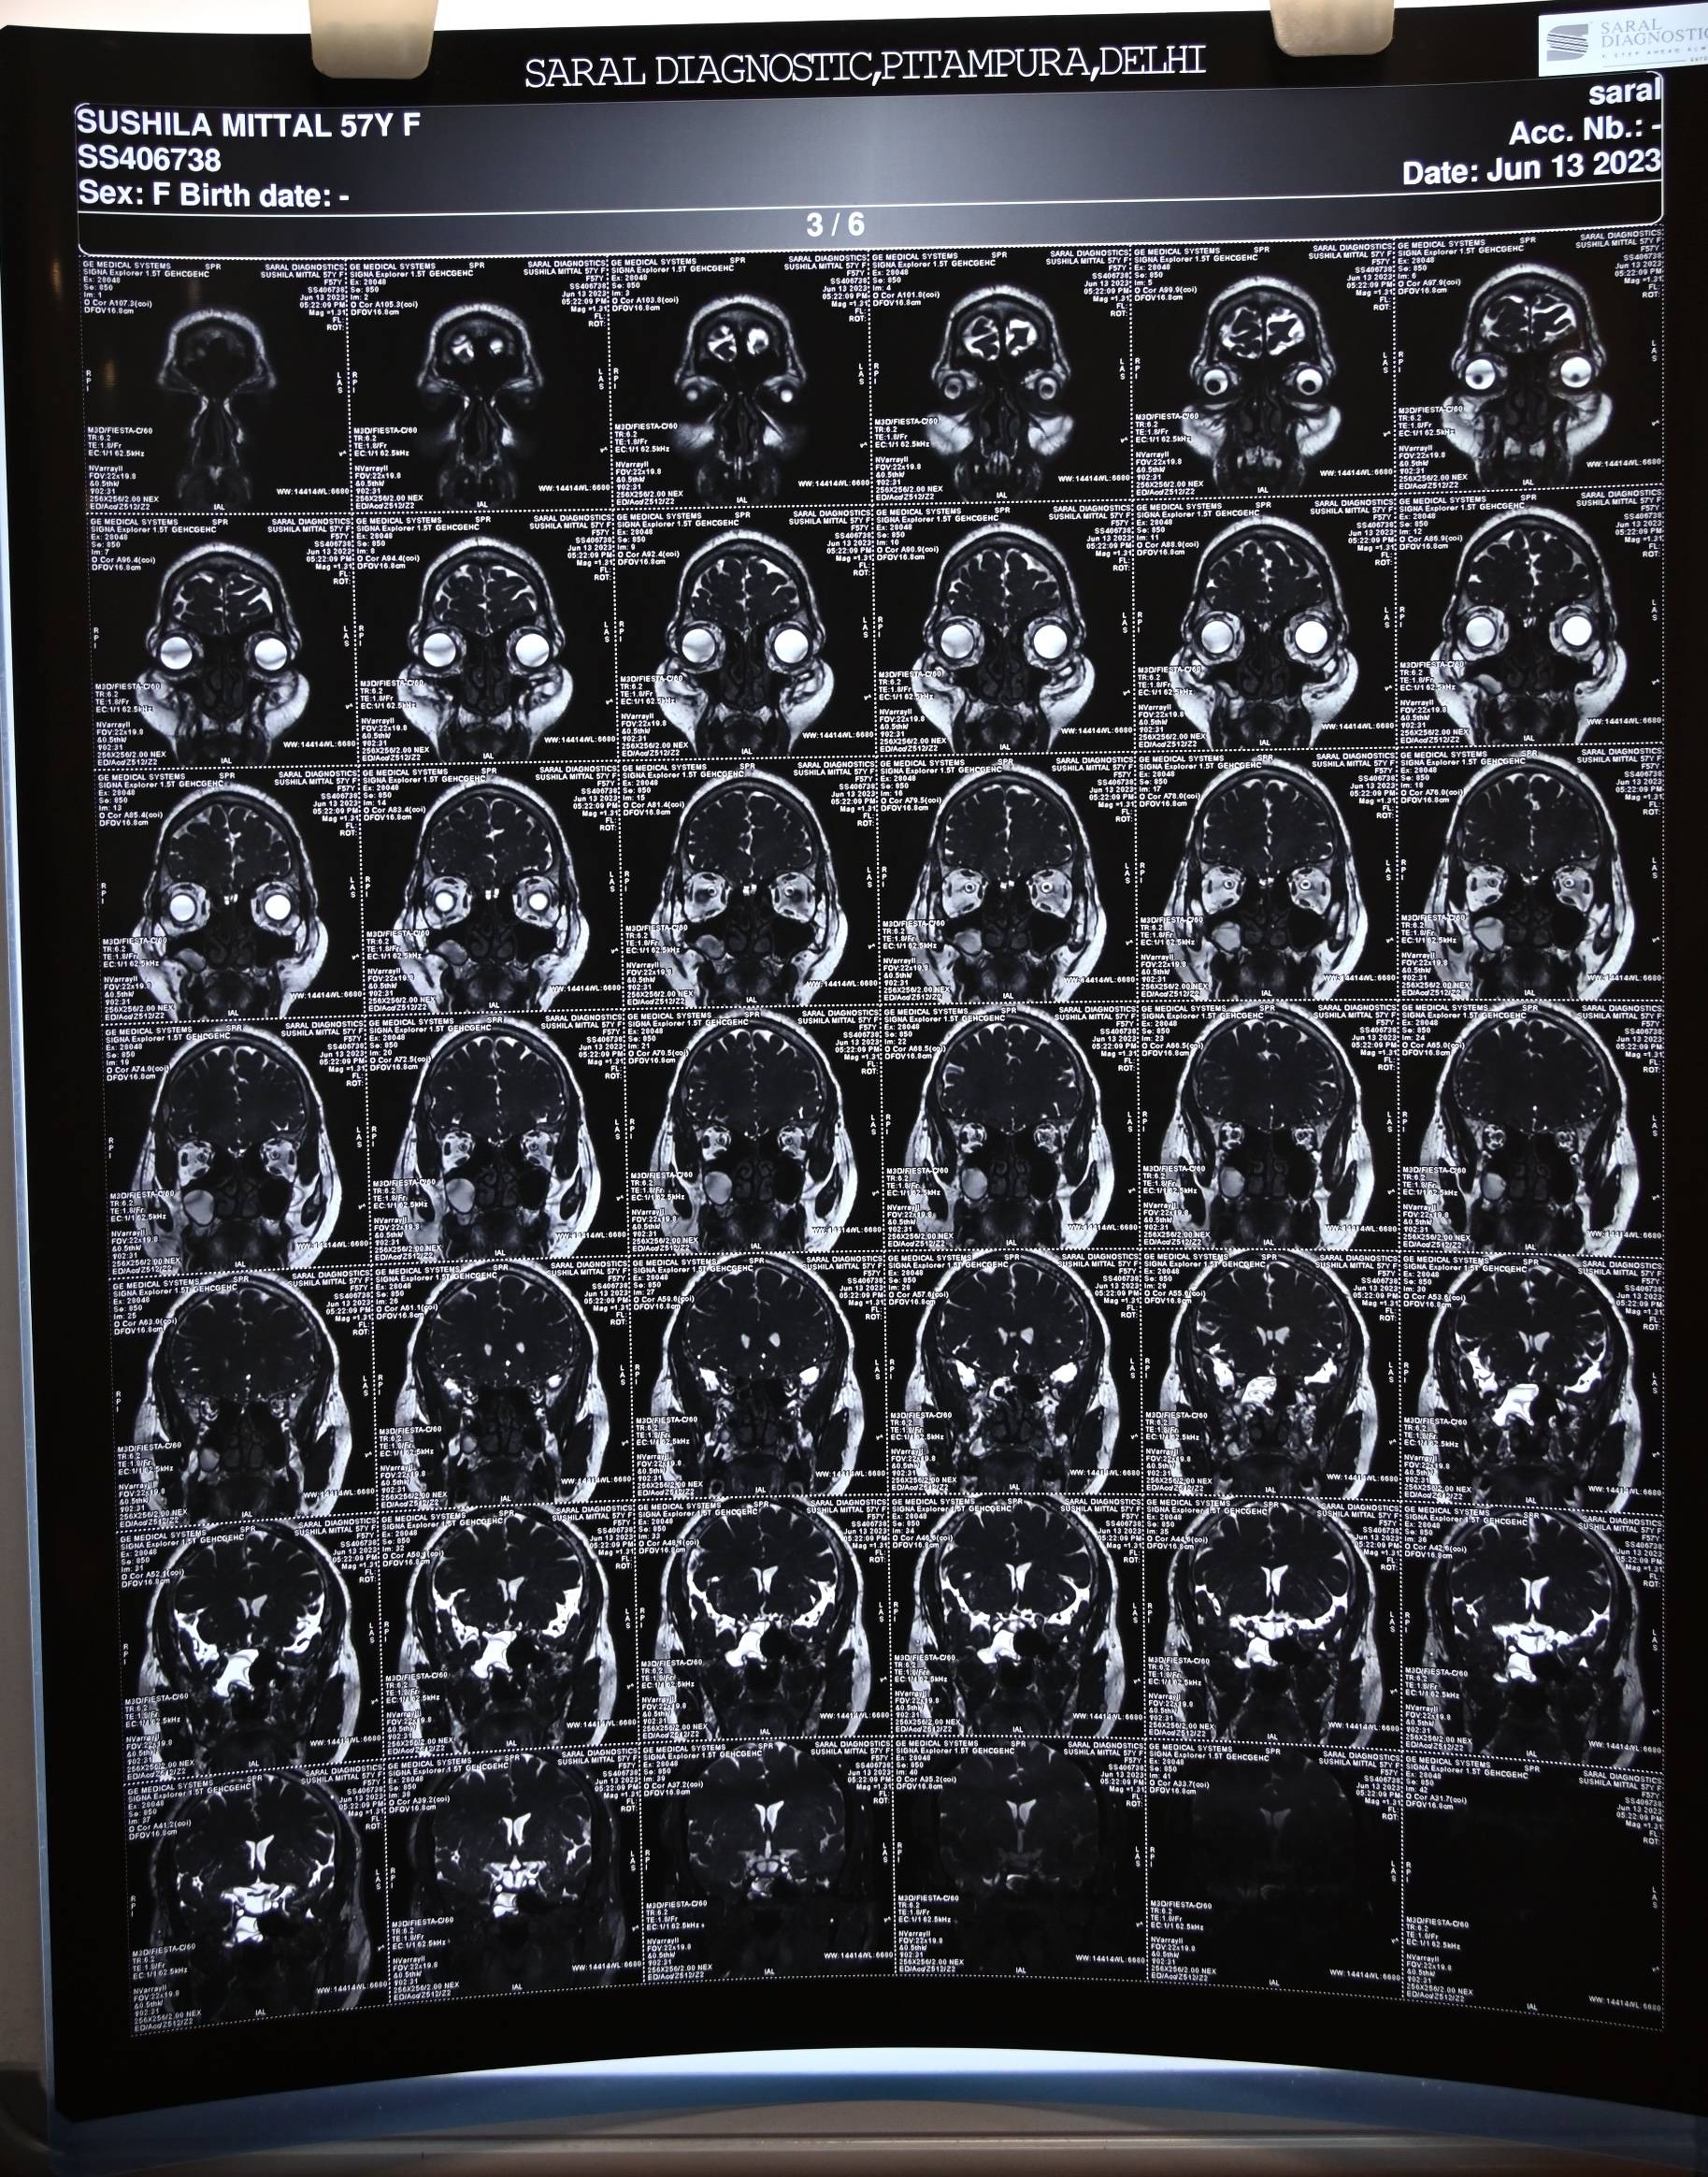

The patient was examined by an ENT surgeon and underwent an MR cisternography with contrast, which confirmed the clinical diagnosis. The report revealed two osseo-dural defects along the posterior wall of the lateral recess of the right sphenoid sinus, measuring approximately 3.1 mm and 2.4 mm, with small herniations of brain parenchyma measuring about 5 mm at both sites. The right sphenoid sinus and its lateral recess were filled with fluid revealing an isointense signal to CSF.